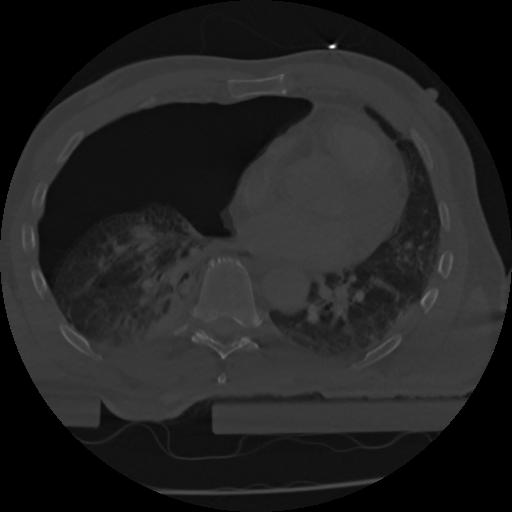

22 ANGIO,CE,Vol,0.5,ANGIO,,